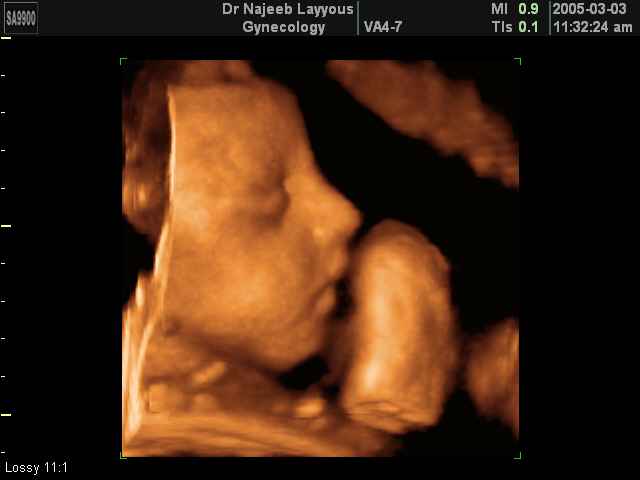

- 3D Fetal Profile Ultrasound Scan Photos

3D Fetal Profile Ultrasound Scan Photos | Dr N Layyous